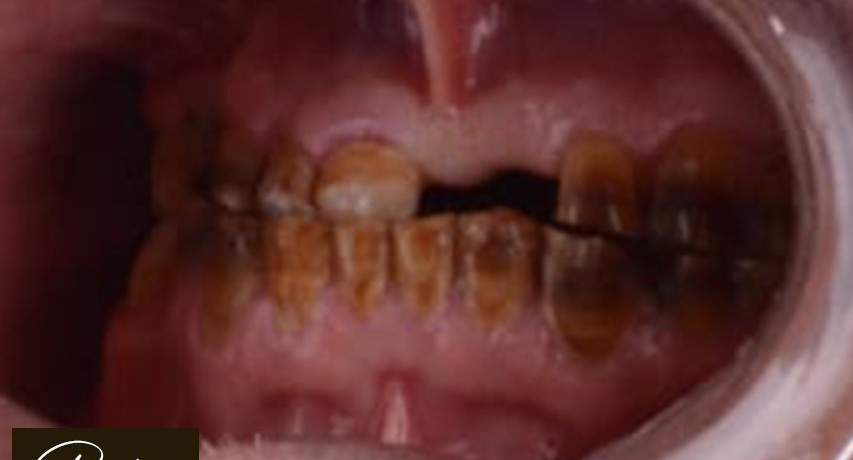

د. حنان ابو الحسن ، مؤسسة Lavender Aesthetic Clinics، هي طبيبة أسنان متخصصة في تركيبات الاسنان ,زراعة الاسنان , حشو عصب ,حشو تجميلي

تميزت برؤيتها اللي بتركز على الجمع بين العلاج الدقيق واللمسة التجميلية، عشان تقدم للمرضى تجربة علاجية مختلفة تجمع بين الصحة، الراحة، والجمال.